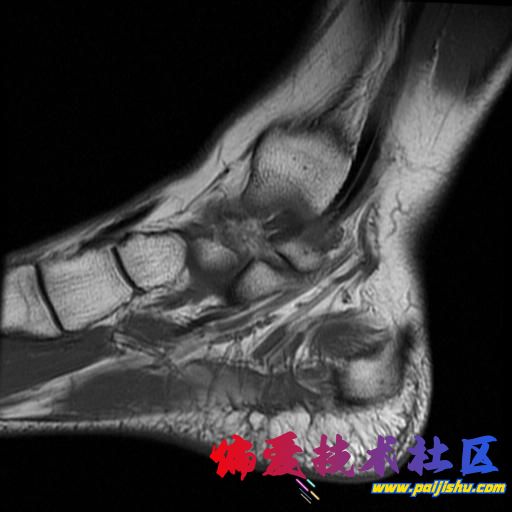

庆幸骨头没事,单肌腱拉伤,静养中